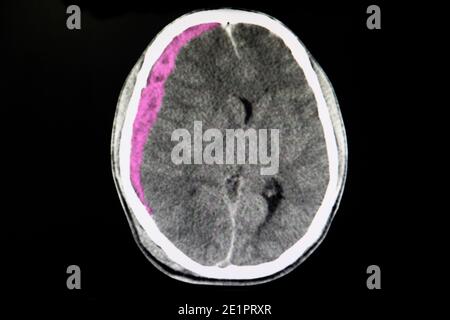

Emorragia Subdurale Con L Edema Del Cervello Fotografia Stock Immagine Di Testa Voluminoso